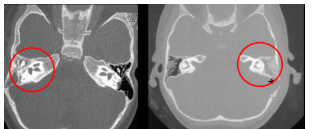

Dx de la siguiente imagen

A

Mastoiditis

Clave en imagneología para dx de mastoiditis

Opacificación de celdillas mastoideas+ colección de líquido (pus o moco)

Si es crónico vemos efecto esclerodiploico que es mastoides osificada